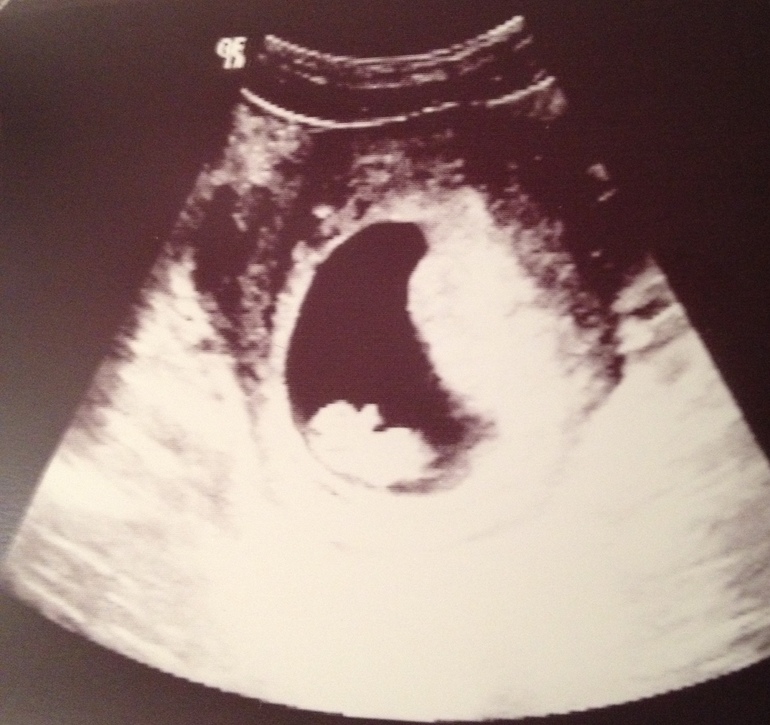

Сегодня увидела свою лялечку на УЗИ!

В общем, сегодня же записалась на УЗИ и в этот же вечер сходила. Муж тоже примчался ко времени, так что свидание было втроём!

Главное - всё у нас хорошо! Сердечко бьётся 175 уд. в минуту, КТР 26 мм. Желточный мешочек диаметром 4 мм. Плодное яйцо - 50 мм. Яичники без особенностей. По срокам всё соответствует. Сказали, 9 недель - ближе к 10-ти. А сегодня у нас как раз 9.4.

Это из медицинских фактов. А из душевного - мы наконец увидели свою лялечку!

Она ёрзала и махала нам ручкой )) Сей момент даже удалось запечатлеть!

И поняла, почему у меня тянущие ощущения бывают именно слева. Оказывается, прикрепился мой малыш по левой боковой стенке. Теперь можно успокоиться до скрининга в двадцатых числах декабря.